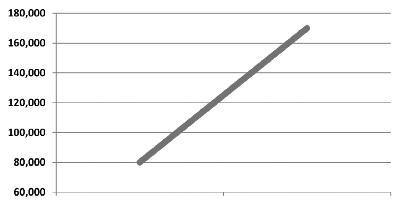

n. 2: l’incidenza del cancro è ancora in crescita

nonostante tutte le montature mediatiche sulle ‘scoperte’ mediche

Cosa significa ciò?

• Se una malattia si diffonde sempre di più, significa che i meccanismi di controllo non sono stati ancora scoperti o non vengono utilizzati nella pratica medica.

• Approcci tradizionali come la chemioterapia e la radioterapia, utilizzati su pazienti affetti da cancro per più di mezzo secolo, evidentemente non sono riusciti a frenare la diffusione del cancro.

• Quindi, la chemioterapia e le radiazioni non possono essere considerati una soluzione credibile per impedire la diffusione del cancro.

• Pertanto, vi è urgente bisogno di nuovi approcci efficaci per controllare la crescente diffusione del cancro!

Aumento del numero dei decessi dovuti al cancro nei diversi gruppi di età, dal 1970 al 2000

Età dei pazienti 70 - 79 anni

Età dei pazienti 60 - 69 anni

Età dei pazienti 50 - 59 anni

Dati statistici per gli USA, dati comparabili per l’Europa. Fonte: Journal of the American Medical Association, 2005